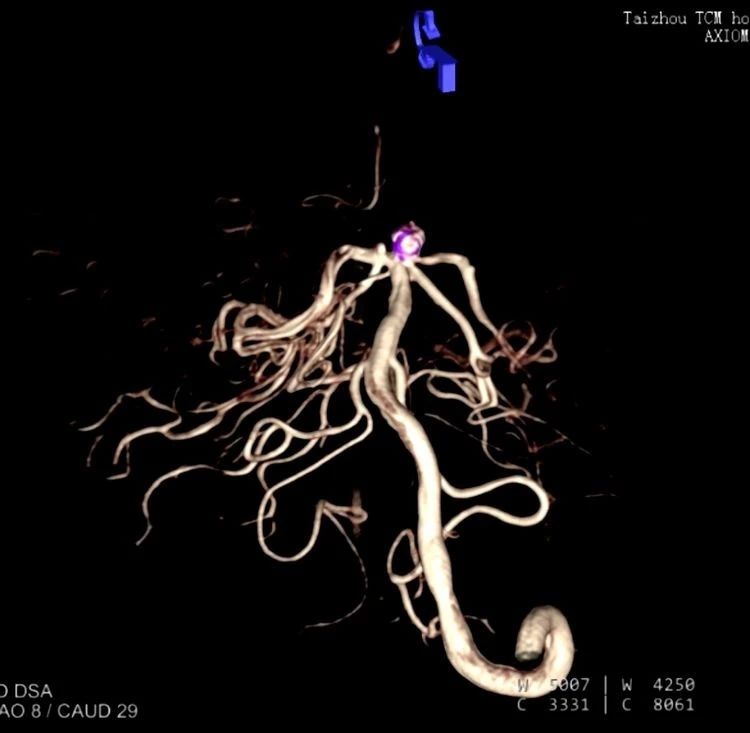

術(shù)中影像重建顯示的不同角度的動脈瘤,看起來很漂亮哦